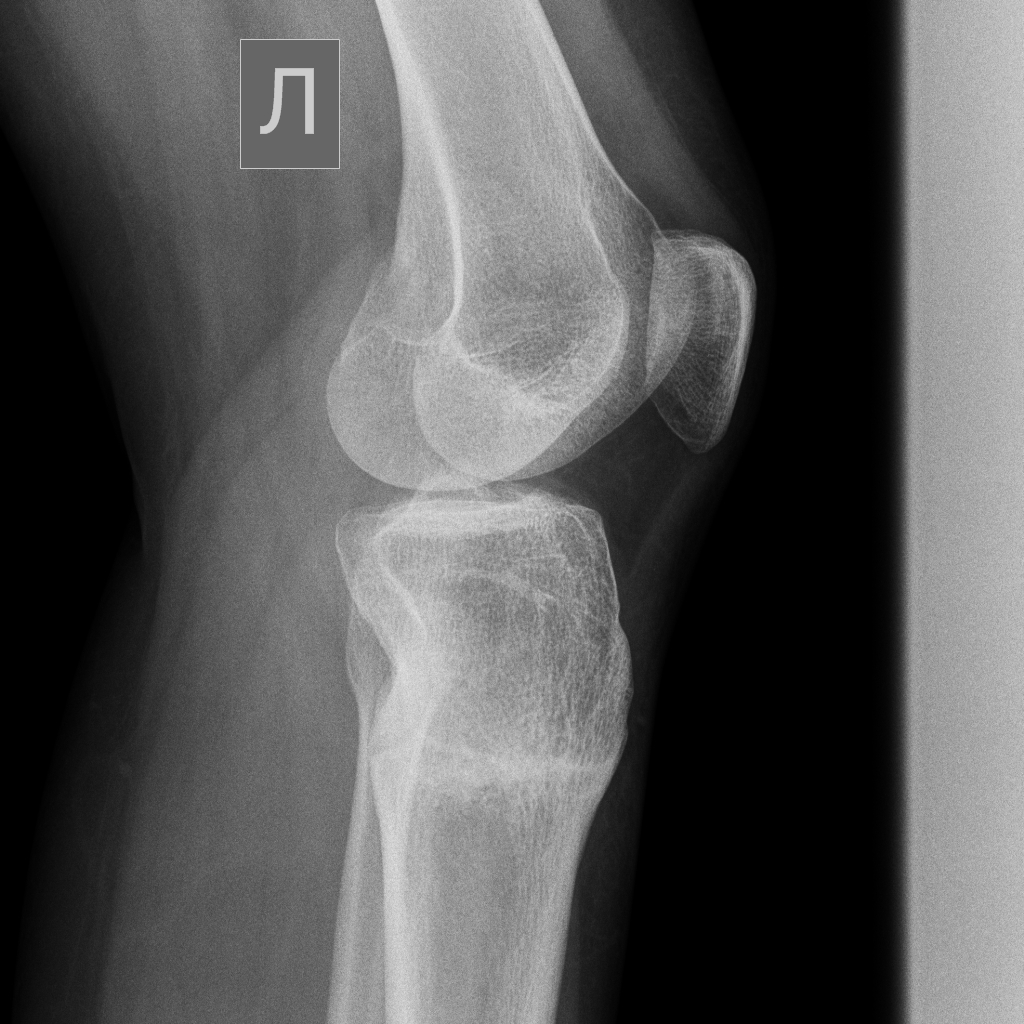

Дата операции 11.03.2014г.

Дата снятия аппаратов 10.06.2014г.

Срок лечения 3 месяца.